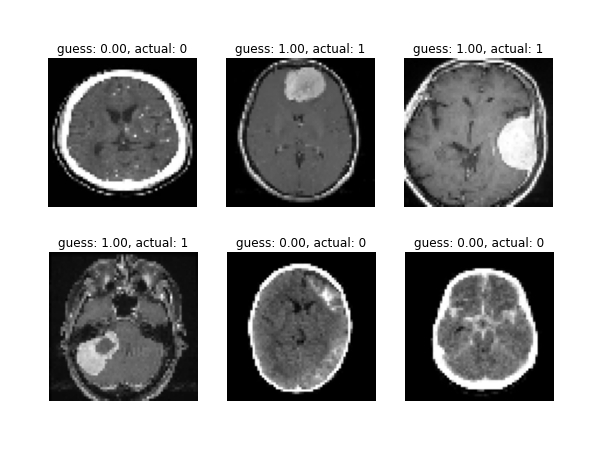

Brain MRI Classifier

Machine Learning

Python

TensorFlow